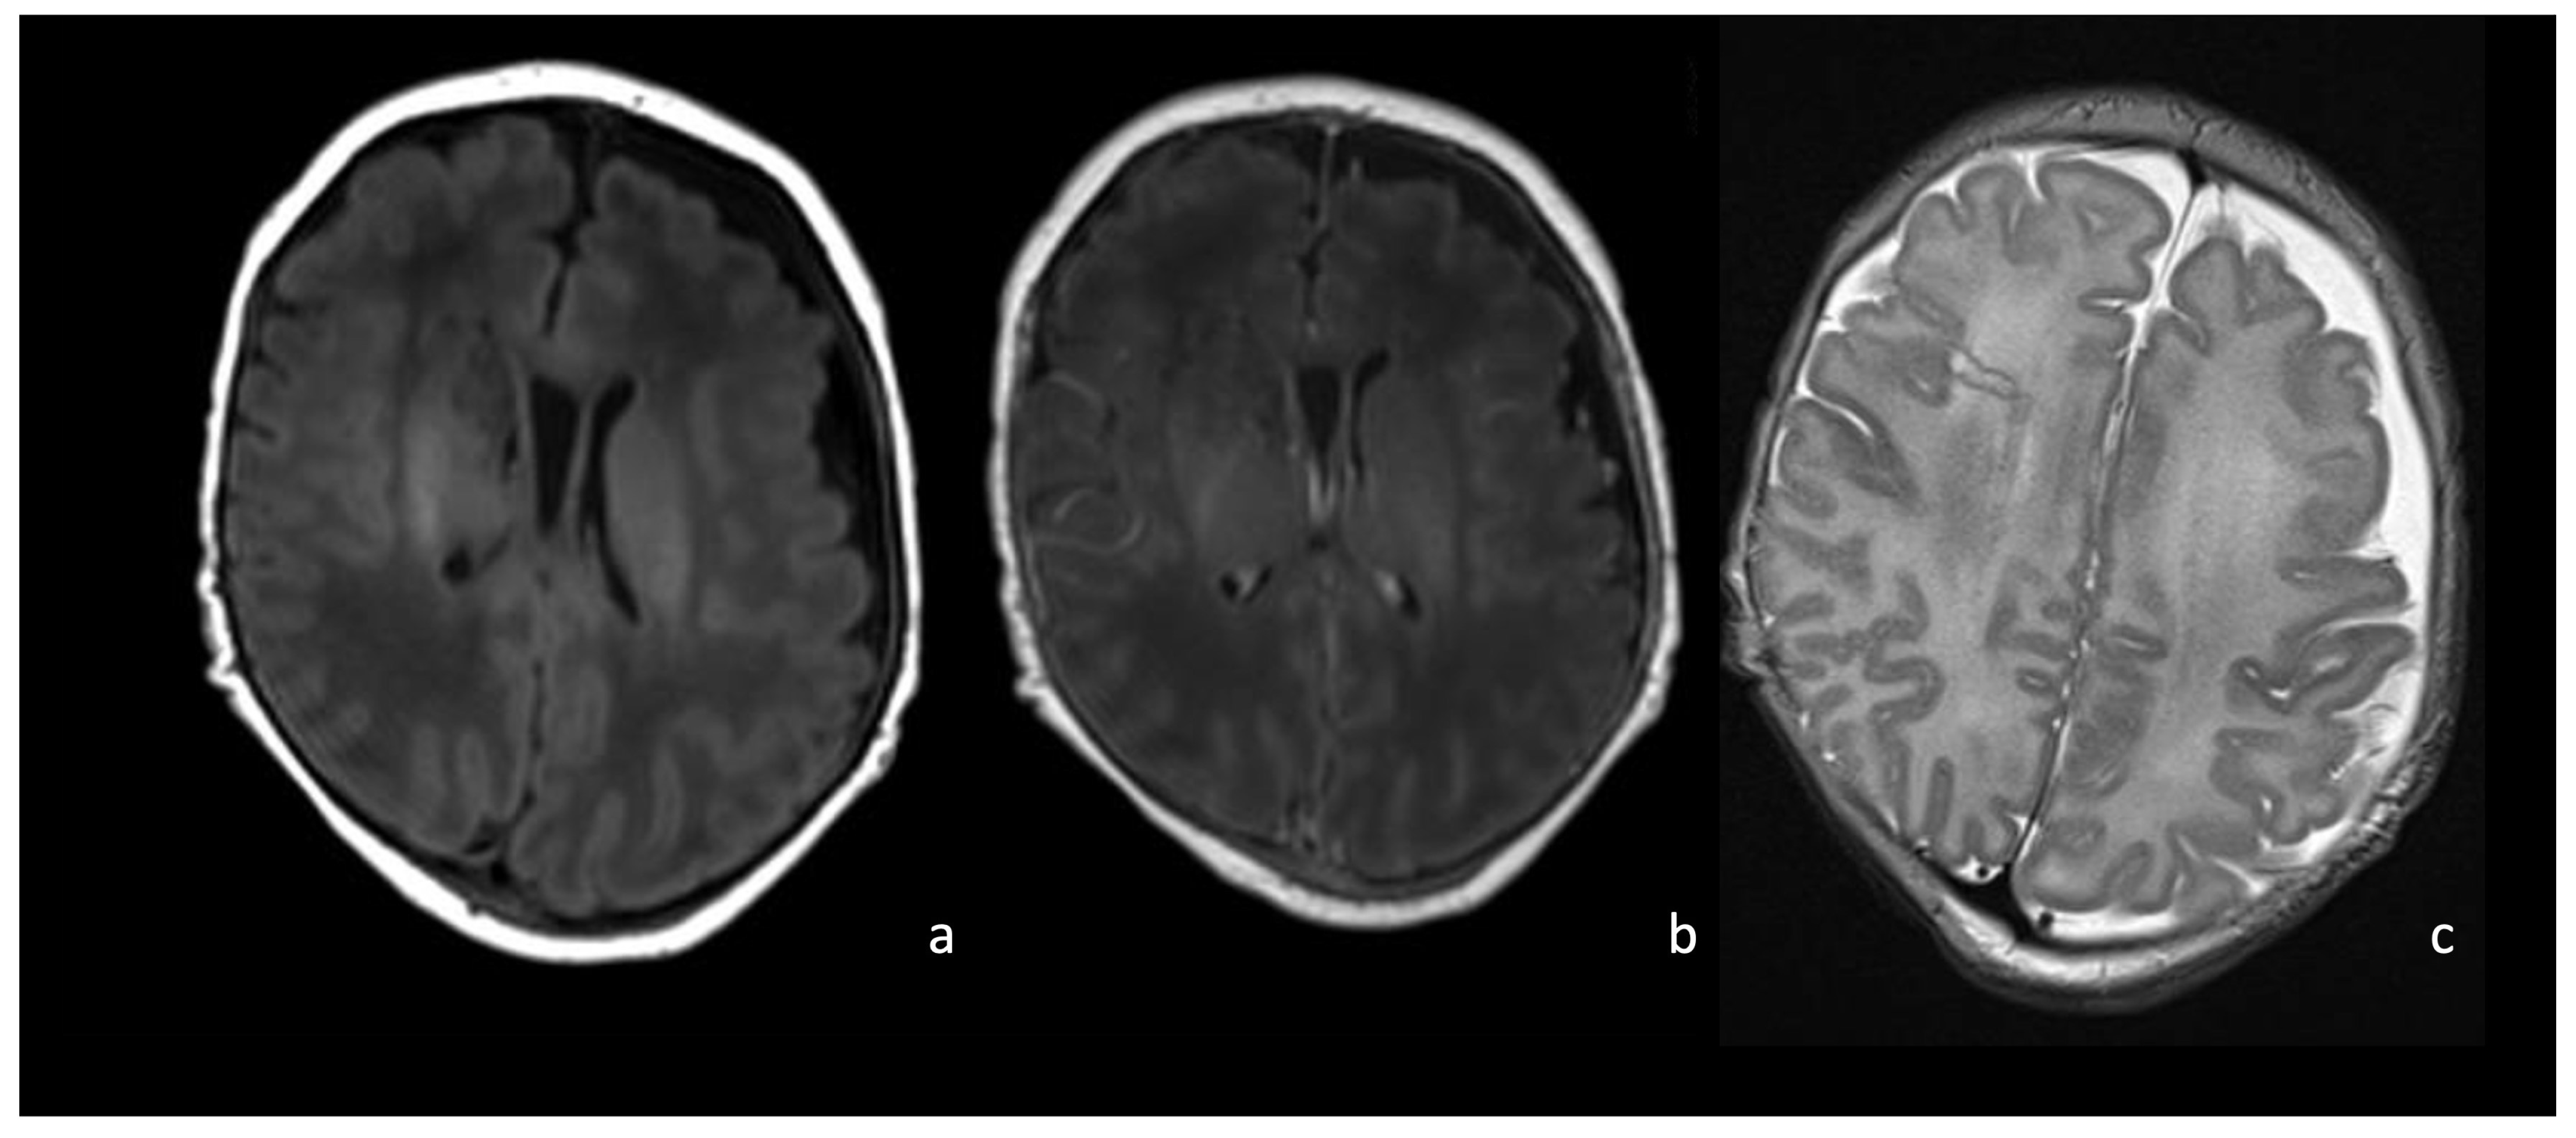

5.1. Choroid Plexitis and Ventriculitis

5.3. Ventriculomegaly and Hydrocephalus

5.4. Effusions and Empyema